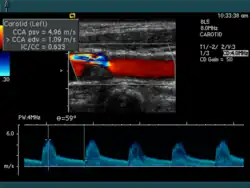

Liegen Stenosen an den arteriellen Beingefäßen vor, spricht man von der peripheren arteriellen Verschlusskrankheit. Es kommen auch Stenosen an den Nierenarterien (Nierenarterienstenose), den Iliakalgefäßen und an den Halsgefäßen (Carotisstenose) vor. Letztere stellen ein Risiko für einen Hirninfarkt durch Gefäßverschluss oder arterielle Embolie dar.

Zur Diagnostik werden Sonografie bzw. Stressechokardiografie, digitale Subtraktionsangiografie bzw. Koronarangiographie, Magnetresonanzangiografie und Computertomografieangiografie eingesetzt.